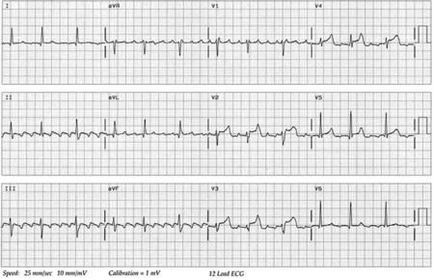

Introduce tu texto aquí... SCACEST Lateral